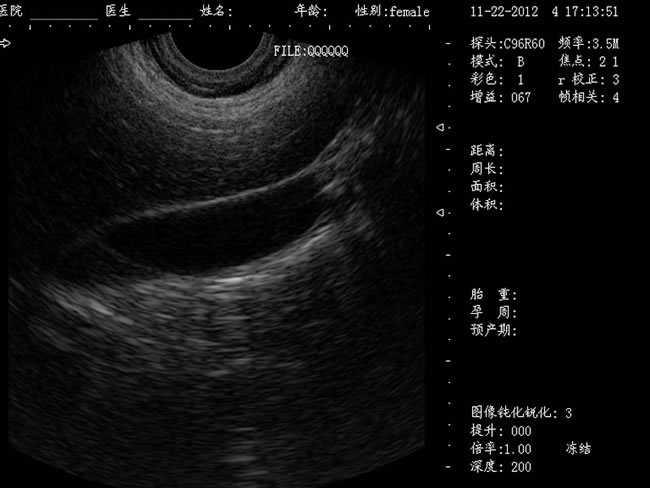

定位精確 手術效率高:實時動態頻率掃描等全數字超聲成像技術、生成精確的圖像引導手術器械迅速到大手術位置,避免損傷子宮內膜和子宮穿孔的現象,即減輕了患者的痛苦又極大提高了手術效率。

CXA10R/6.5MHz 腔內探頭

選配:CXA60R/3.5MHz 凸陣探頭

隨著醫療技術水平的提高,目前婦產科手術中所應用的相關設備也有了加大的改進。尤其是在人工流產手術中,將B超婦產科手術監視儀應用到手術過程中,彌補傳統手術中所采用設備的不足之處,減輕手術中患者的疼痛感覺,使得手術順利的完成。這種儀器相比于傳統的儀器來說,其在操作上更為方便和簡單,能夠對妊娠反應有很好的療效。